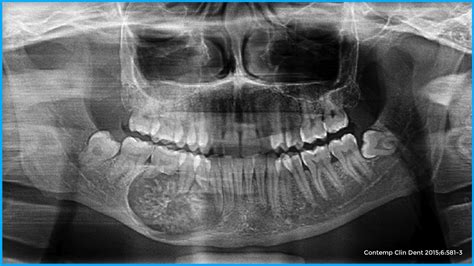

Hiperplasia gingival. No es propiamente una tumoración, pero puede llegar casi a ocultar los dientes (fig. 8). Presenta un aumento de las fibras colágenas y puede ocurrir sin una causa conocida o inducida por medicamentos, especialmente antiepilépticos (fenitoína) y ciclosporina, pero también verapamilo, nifedipino, diltiazem y otros muchos. Conviene diferenciarla también de la fibromatosis gingival hereditaria, los infiltrados en el curso de una leucemia y la hiperplasia gingival por falta de cuidados en la zona.